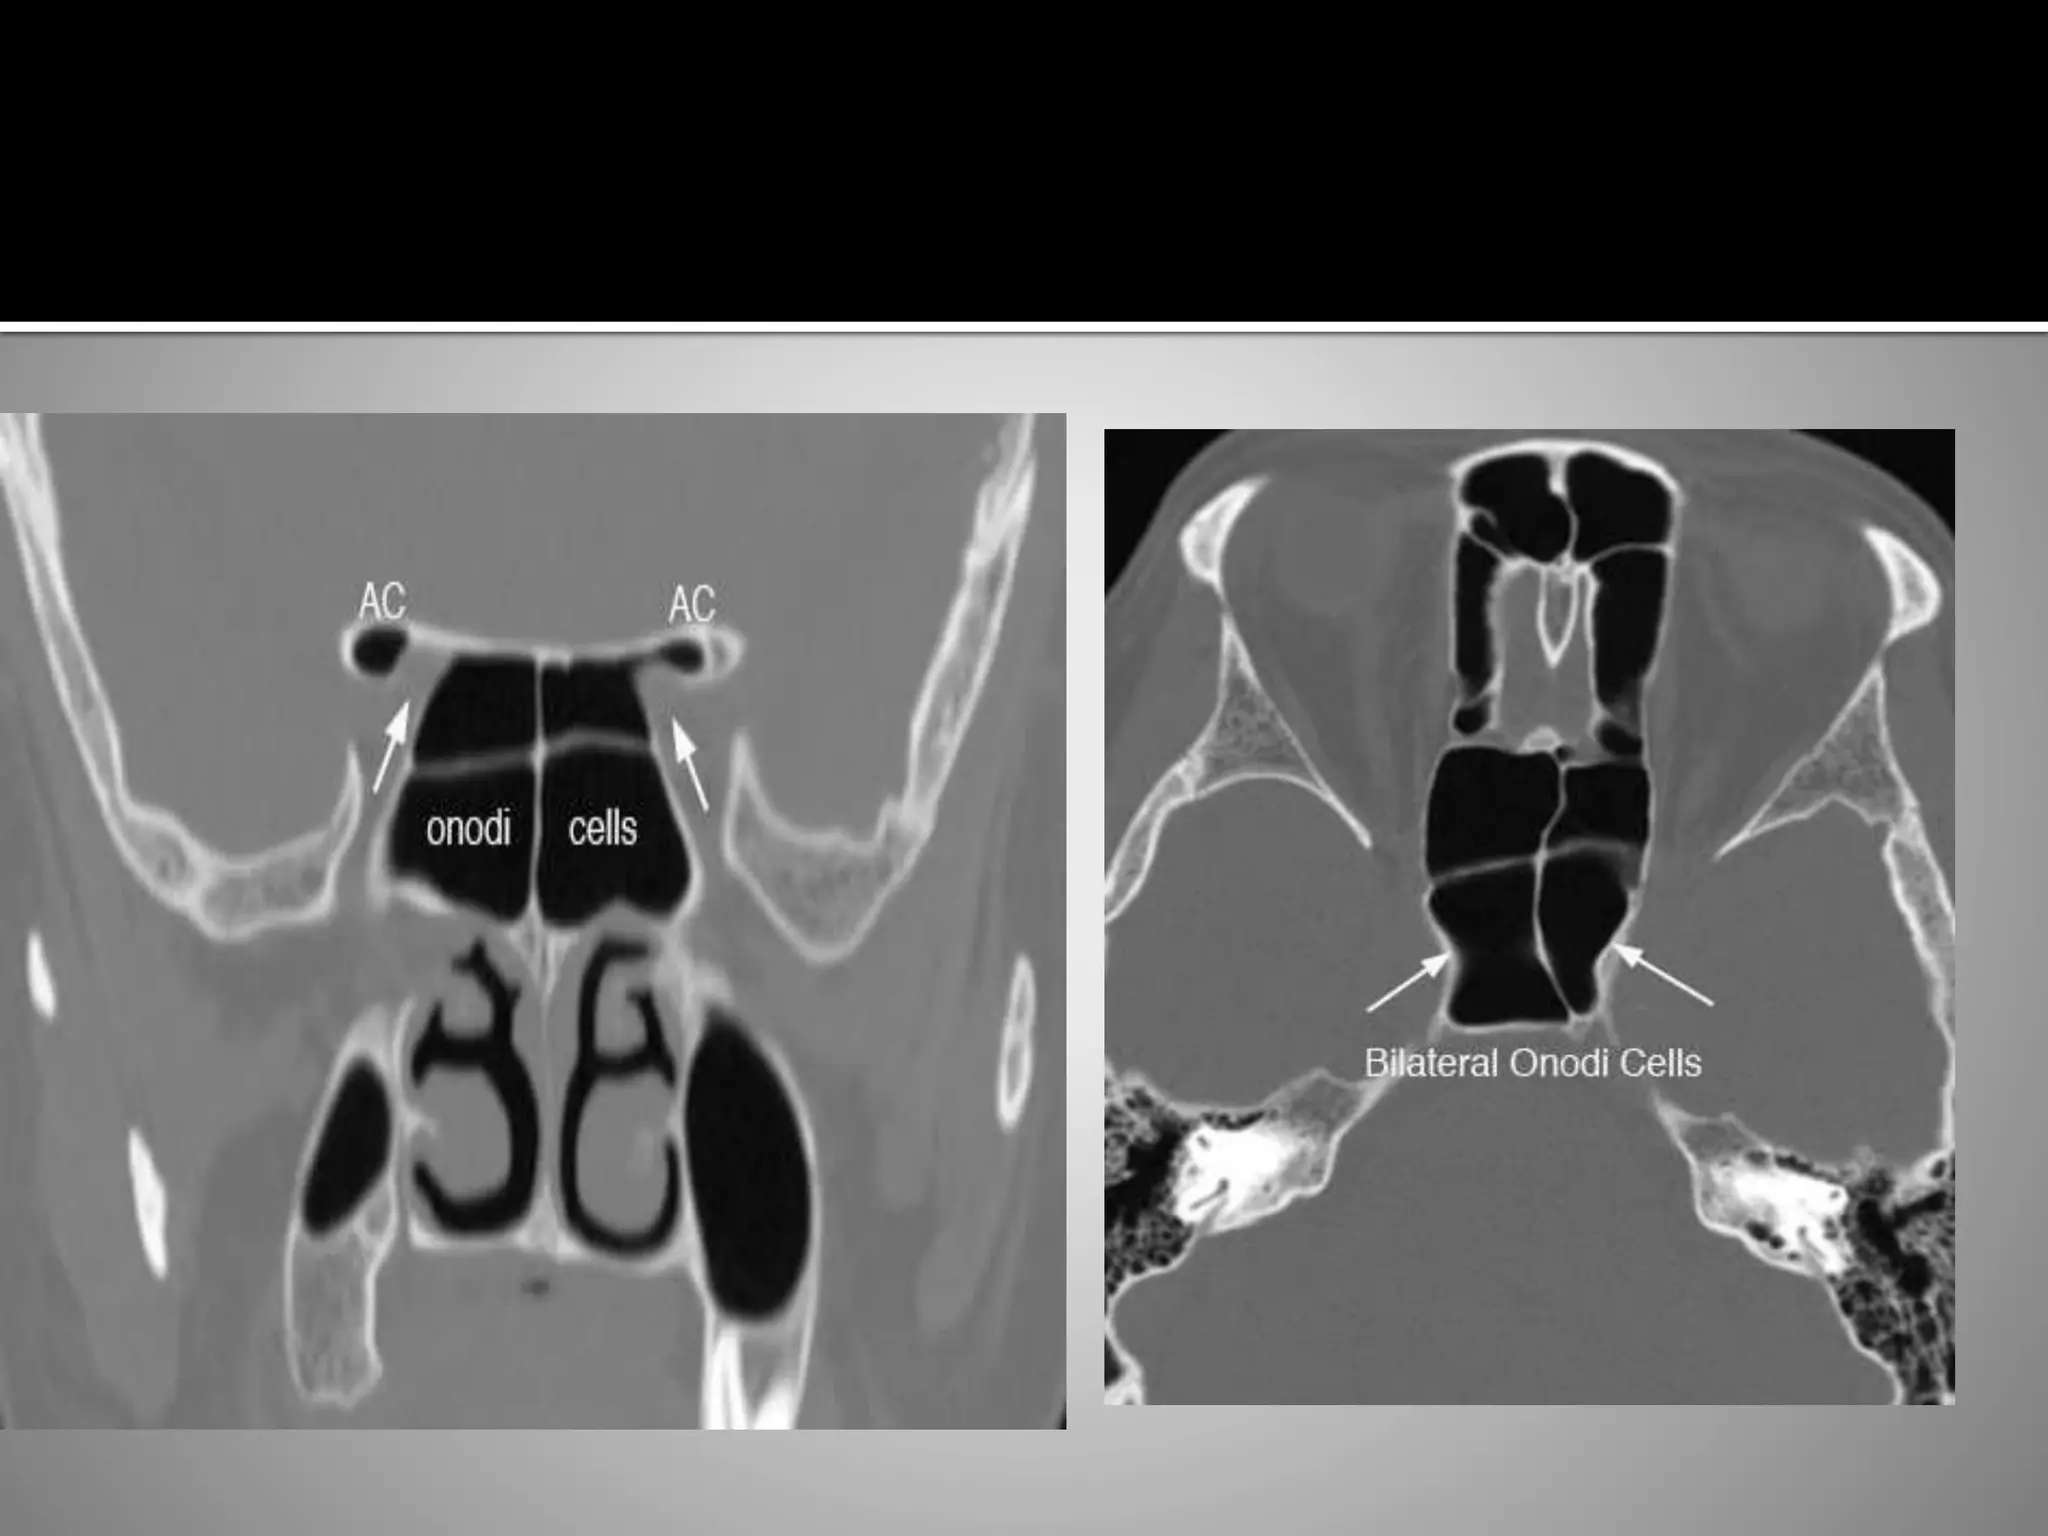

 Two definitions of Onodi cells.

 The first defines them as the most

posterior ethmoid cells, being

superolateral to the sphenoid sinus and

closely associated with the optic nerve.

 Another, more general description

defines Onodi cells as posterior ethmoid

cells extending into the sphenoid bone,

situated either adjacent to or impinging

upon the optic nerve